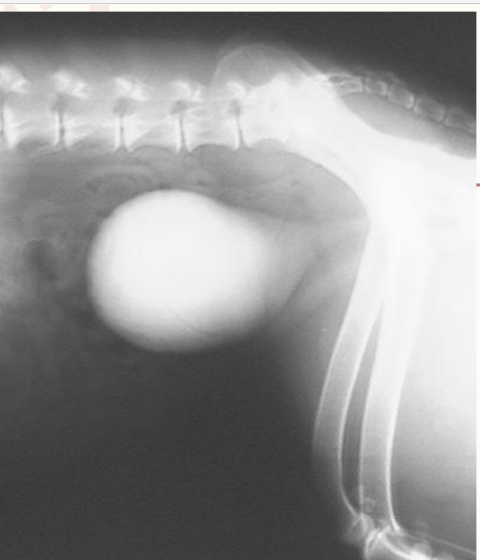

Double contrast, what is it?

A radiographic contrast technique that uses a combination of both positive & negative-contrast media simultaneously.